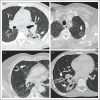

Pulmonary cystic echinococcosis

Purpose of review: The aim of our review is to summarize specific clinical, diagnostic and treatment aspects of pulmonary cystic echinococcosis. The lung is the organ second most affected by cystic echinococcosis with approximately a quarter of cystic echinococcosis cysts. Most cysts are in the liver. Apart from the watch and wait approach for selected inactive cysts [cystic echinococcosis CE4, CE5], the well established WHO cystic echinococcosis cyst classification-based treatment of hepatic cystic echinococcosis cannot be applied to pulmonary cystic echinococcosis cysts. Some standard interventions can even be harmful when applied to pulmonary cystic echinococcosis cysts.